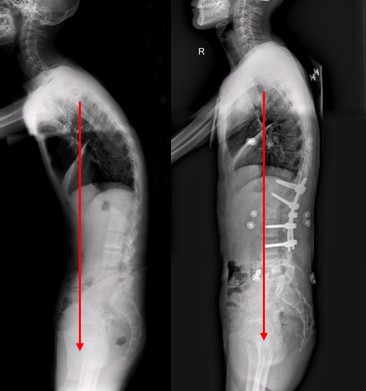

医生说:强直性脊柱炎疾病虽然是一种致残率很高的疾病,但是只要进行积极正规的治疗,在发病初期完全可以治疗疾病的,中期可以实现控制病情,保护受累关节,晚期治疗多半能恢复到自理生活或者具备轻微的劳动能力。由此可见,强直性脊柱炎疾病严重不严重不能一概而论,而应根据病情来确定。